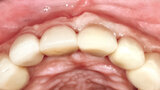

Fig. 12b: The occlusal view illustrated the cervical tissue volume and contours.